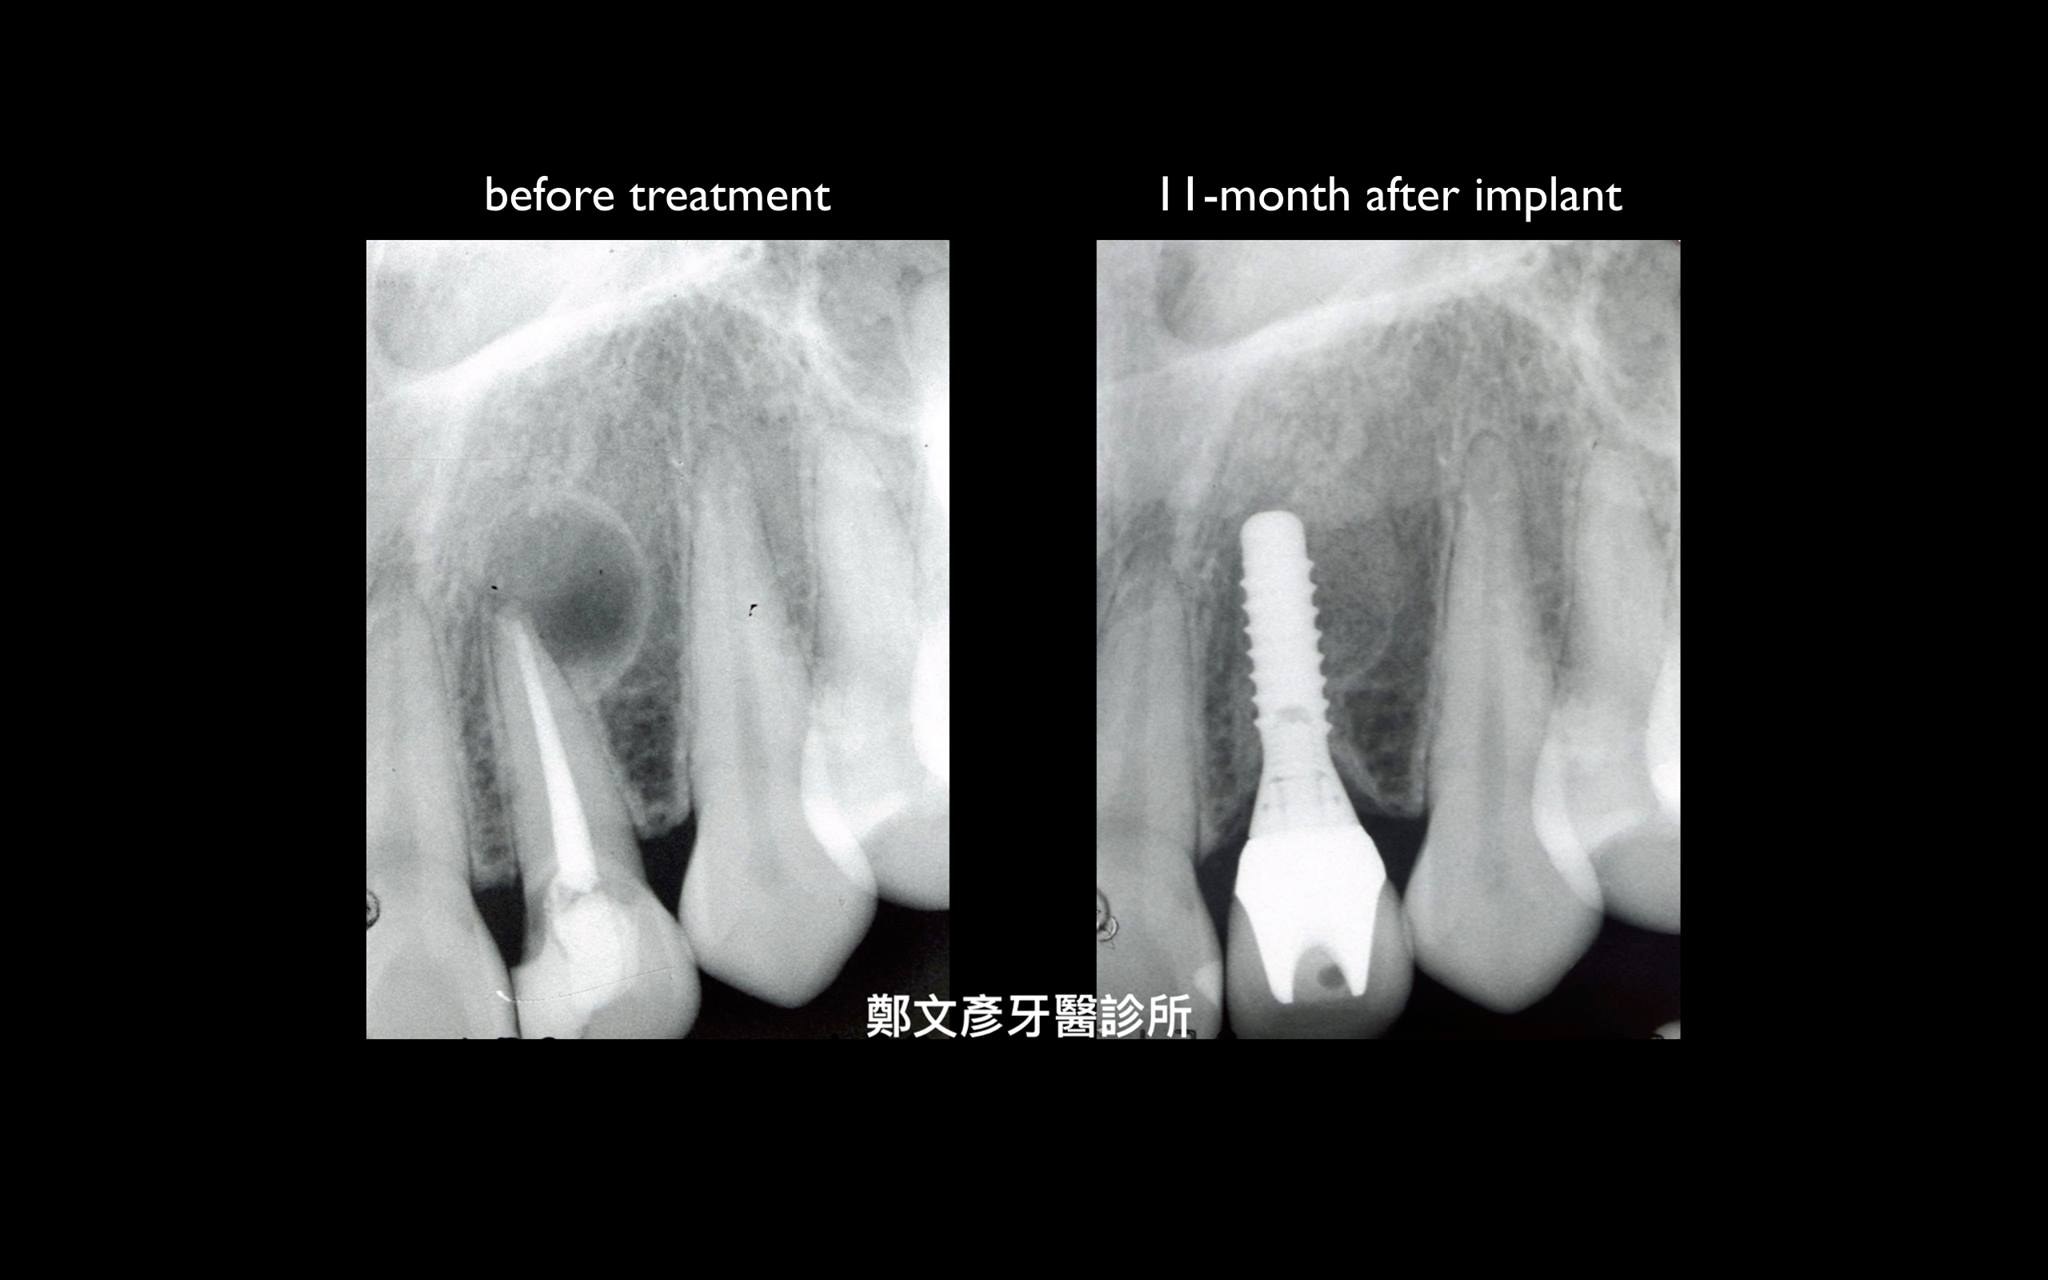

前牙植牙美學及軟組織轉移

植牙美學